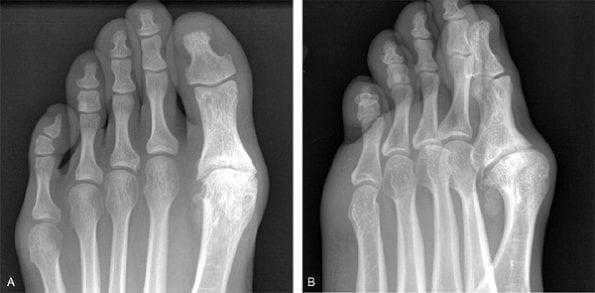

(Левый) При прицельной рентгенографии 1-го плюснефалангового сустава в передне-задней проекции определяется травматическая вальгусная деформация большого пальца стопы. Выявляется отрывной перелом области прикрепления медиальной коллатеральной связки к основанию проксимальной фаланги. С медиальной стороны наблюдается отек мягких тканей. Визуализируется отведение проксимальной фаланги большого пальца стопы, однако для установления давности деформации необходимо знать анамнез.

(Правый) При рентгенографии стопы в передне-задней проекции выявляется проксимальное смещение сесамовидных костей вследствие разрыва подошвенной связки. С медиальной стороны наблюдается отек мягких тканей. (Левый) Рентгенография стопы в боковой проекции выполнена в положении пациента стоя на носках. Определяются гипермобильность и дорсальный подвывих 1 -го плюснефалангового сустава вследствие разрыва подошвенной связки. Результаты исследования с нагрузкой оценивать достаточно трудно, поэтому интерпретировать их следует в сравнении со здоровой конечностью.